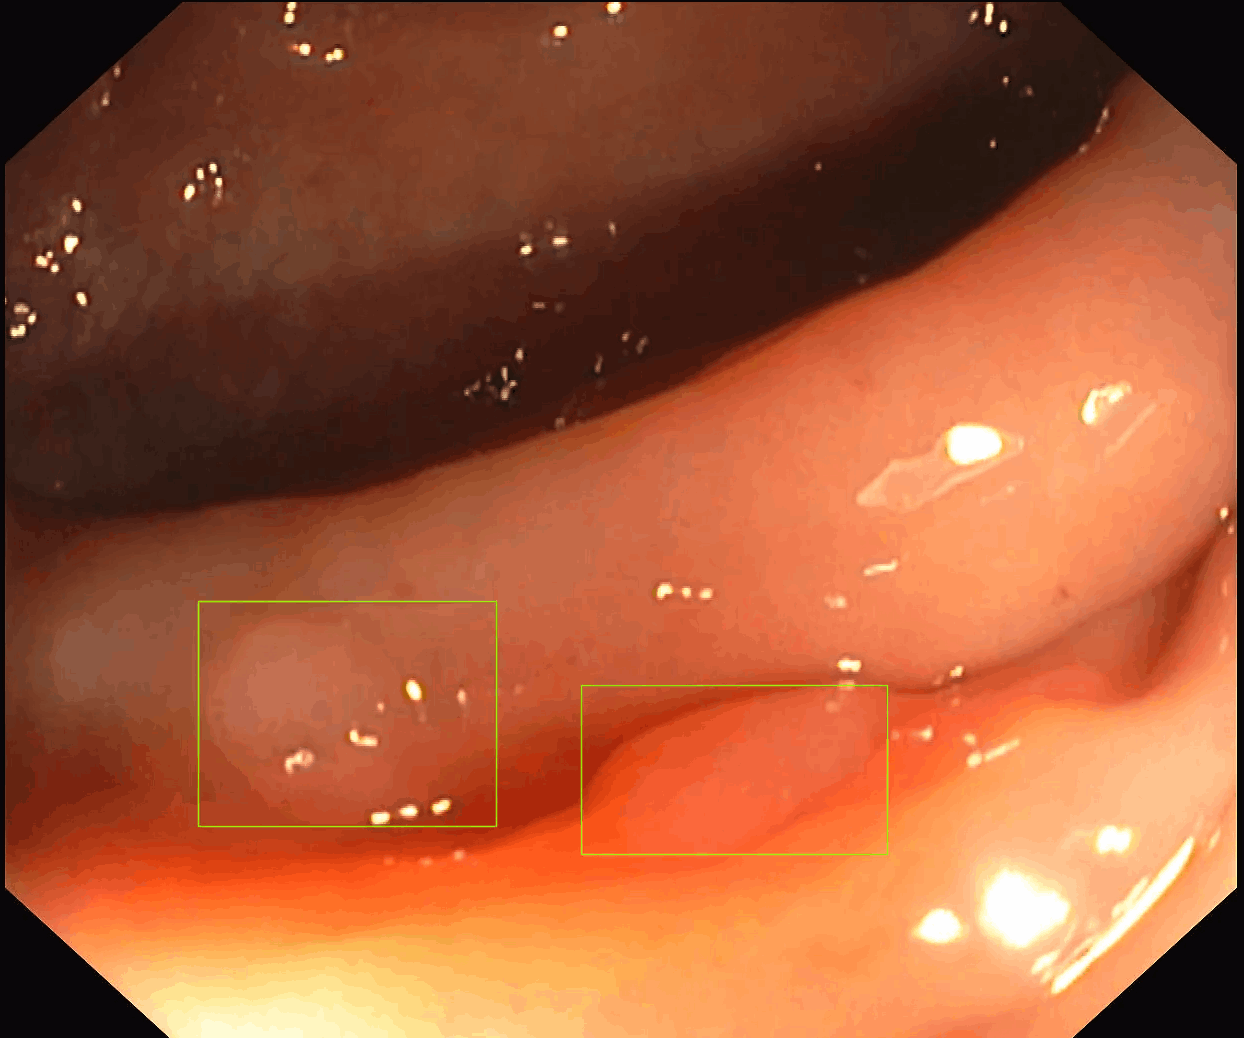

Our first product, SofiOne, is undergoing clinical validation as a decision support tool for the diagnosis of all polyp findings in colonoscopy.